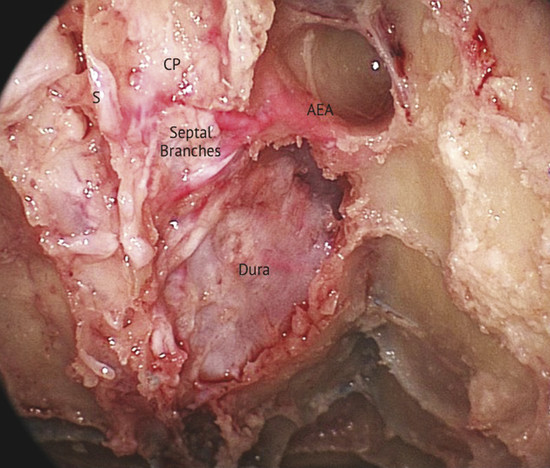

Blood supply of the nasal septum occurs through septal branches of the sphenopalatine artery. Here it anastomoses with branches of the palatine and labial arteries and septal branches of the anterior and posterior ethmoidal arteries; they are easily recognizable in the cranial portion of the septum area (Fig. 13‑1). An anatomical study on the arterial pattern of the nasal septum, traced by microdissection, demonstrated that AEAs were present in all cases, but the posterior ethmoidal arteries in some cases were absent. 1 These arteries, with the middle septal branch of the sphenopalatine artery and the superior labial branch of the facial artery, mainly contribute to the anastomotic triangle of the anterior septum. Only the posterosuperior area is vascularized by the posterior ethmoidal artery branches. 2 The ethmoidal artery originates from the terminal segment of the ophthalmic artery in the orbit cavity, a collateral branch of the internal carotid artery, and passes between the superior oblique and medial rectus muscle. The AEA then reaches the frontoethmoidal suture through the anterior ethmoidal foramen and enters into the anterior ethmoidal canal along with the anterior ethmoidal nerves. The artery crosses the ethmoid roof diagonally from posterolateral to anteromedial (Fig. 13‑2). AEA then divides at the lateral part of the cribriform plate of the ethmoid, giving off two or three branches to the mucosa of the cranial portion of the septum (Fig. 13‑3). Finally, they reach the olfactory cleft and supply terminal branches to the olfactory bulb and the meninges.

One must consider that the septal branches of the AEA are at the same level or just posterior to the septal projection of the axilla of the middle turbinate, as confirmed by a recent anatomical analysis, which showed that the average distance was 7.35 mm (range: 5.5–8.7 mm) and never superior to 1 cm. 3

Bleeding can be seen originating from a septal branch of the AEA, showing a close anatomic relation with the axilla of the middle turbinate (Fig. 13‑4). It is extremely important to consider this anatomical relation during harvesting the flap.

Based on the anatomical criteria of the nasal septum vascularization, characterized by the constant presence of the septal branches of the AEA, we harvested the monolateral mucosal flap with a large and flexible pedicle to bring a suitable blood supply to the flap. The extension to the inferior meatus creates a larger mucosal flap, allowing advancement of the flap without tension. 4

These two aspects, the flap designed without tension and the preservation of the flap’s vascular supply, are the main factors contributing to a high rate of closure.